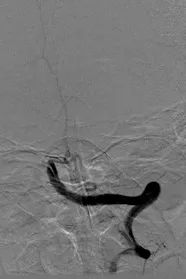

手术前 手术后

穿刺、造影、气管插管全麻、介入开通血管(抽栓、支架取栓、球囊成形),手术时间在1小时左右顺利完成,血管成功开通,术后转带气管导管转重症医学科加强监护、治疗。第二天,患者神志转清,肢体肌力基本恢复正常,停呼吸机、拔除气管导管,评估生命体征平稳后转神经内科继续治疗,结合康复理疗治疗,NIHSS评分由入院时的34分下降为0分,救治效果显著。